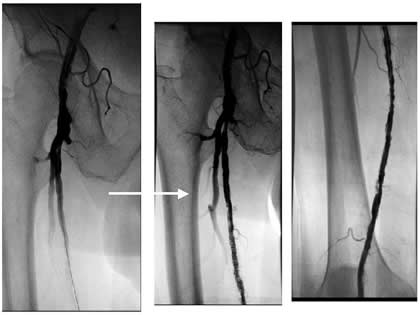

Case 4: A 67-year-old woman with diabetes and tissue loss in the foot secondary to pressure injury with poor healing. Angiogram through an antegrade approach shows a small vessel (average diameter 3 mm) with proximal occlusion and segmental stensoses (Figure 4A). After angioplasty followed by cryoablation, the proximal stenotic areas were treated with 5 mm diameter coronary self-expanding bare stents (Figure 4B). The foot has now healed.

![]() |

| Figure 4A | Figure 4B |